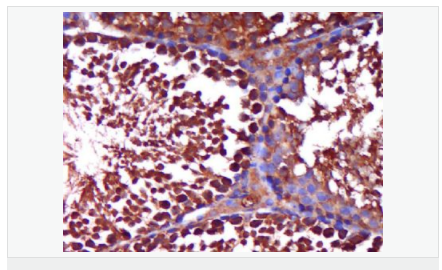

AR是一個由917個氨基酸組成的蛋白質,位于雄激素靶組織細胞中或細胞表面上的特異分子部位或結構。 AR在前列腺癌中起著重要的作用,研究表明AR的表達與組織分型形成一定的相關性 ,AR在高分化的腫瘤中表達較多,而在低分化的腫瘤中表達較少。用于前列腺癌的檢測,指導臨床治療,目前可用于乳腺癌、食道癌等各項腫瘤的研究。